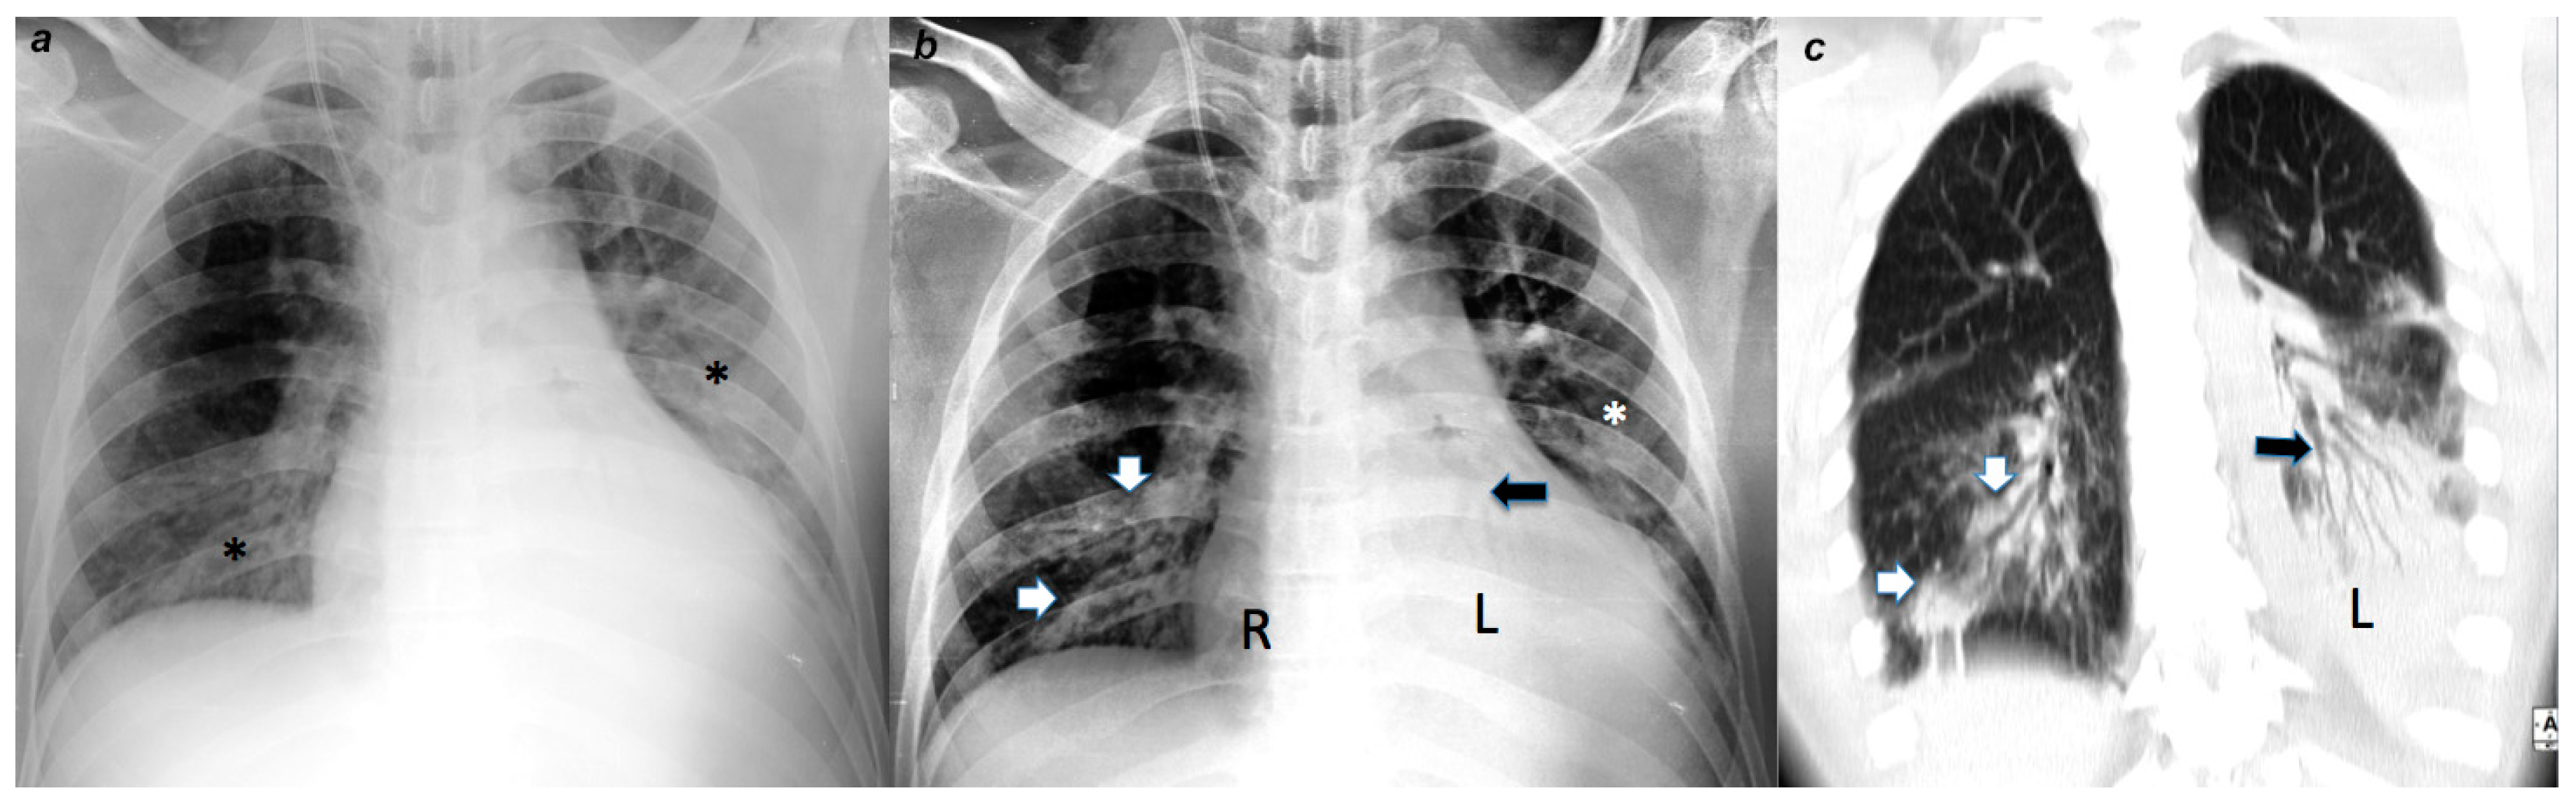

4.2. Radiological Evaluation and Statistics